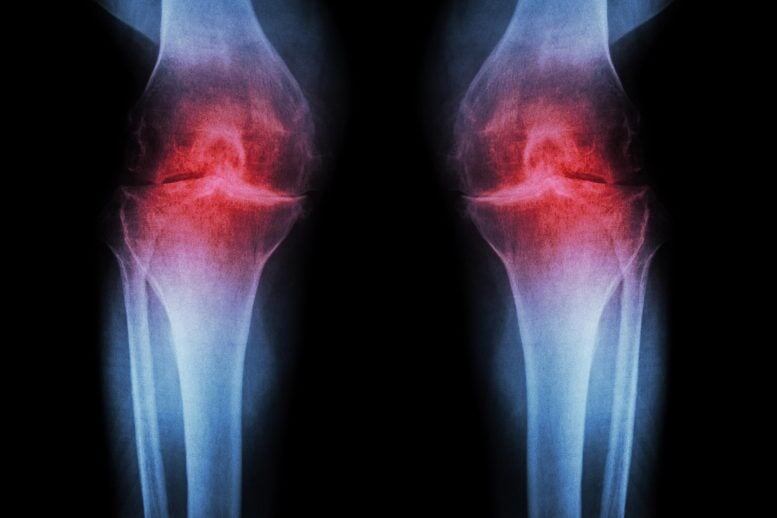

🧠✨Ревматоидный артрит – коварный враг, начинающий свою разрушительную работу задолго до появления первых симптомов. Новое исследование показывает, что иммунная система людей из группы риска претерпевает серьезные изменения за годы до ощутимой боли. Фактически, тело уже ведет невидимую аутоиммунную борьбу. Обнаружены маркеры, позволяющие выявлять болезнь на ранних стадиях, что открывает путь к профилактике и избавлению от многолетних страданий. Осознание того, что артрит начинается гораздо раньше, чем мы думали, может кардинально изменить подход к его лечению. Ранняя диагностика – ключ к победе над болезнью. Возможно, будущее за превентивной медициной? #наука #здоровье #медицина #артрит